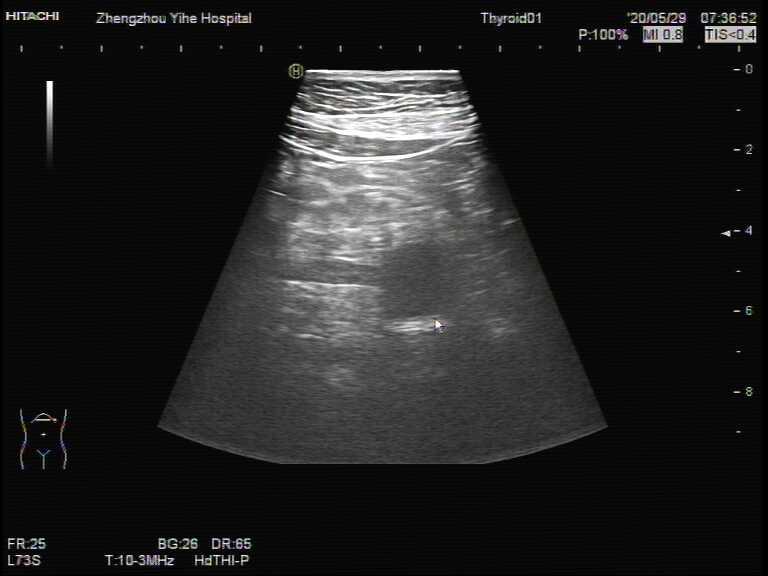

图4